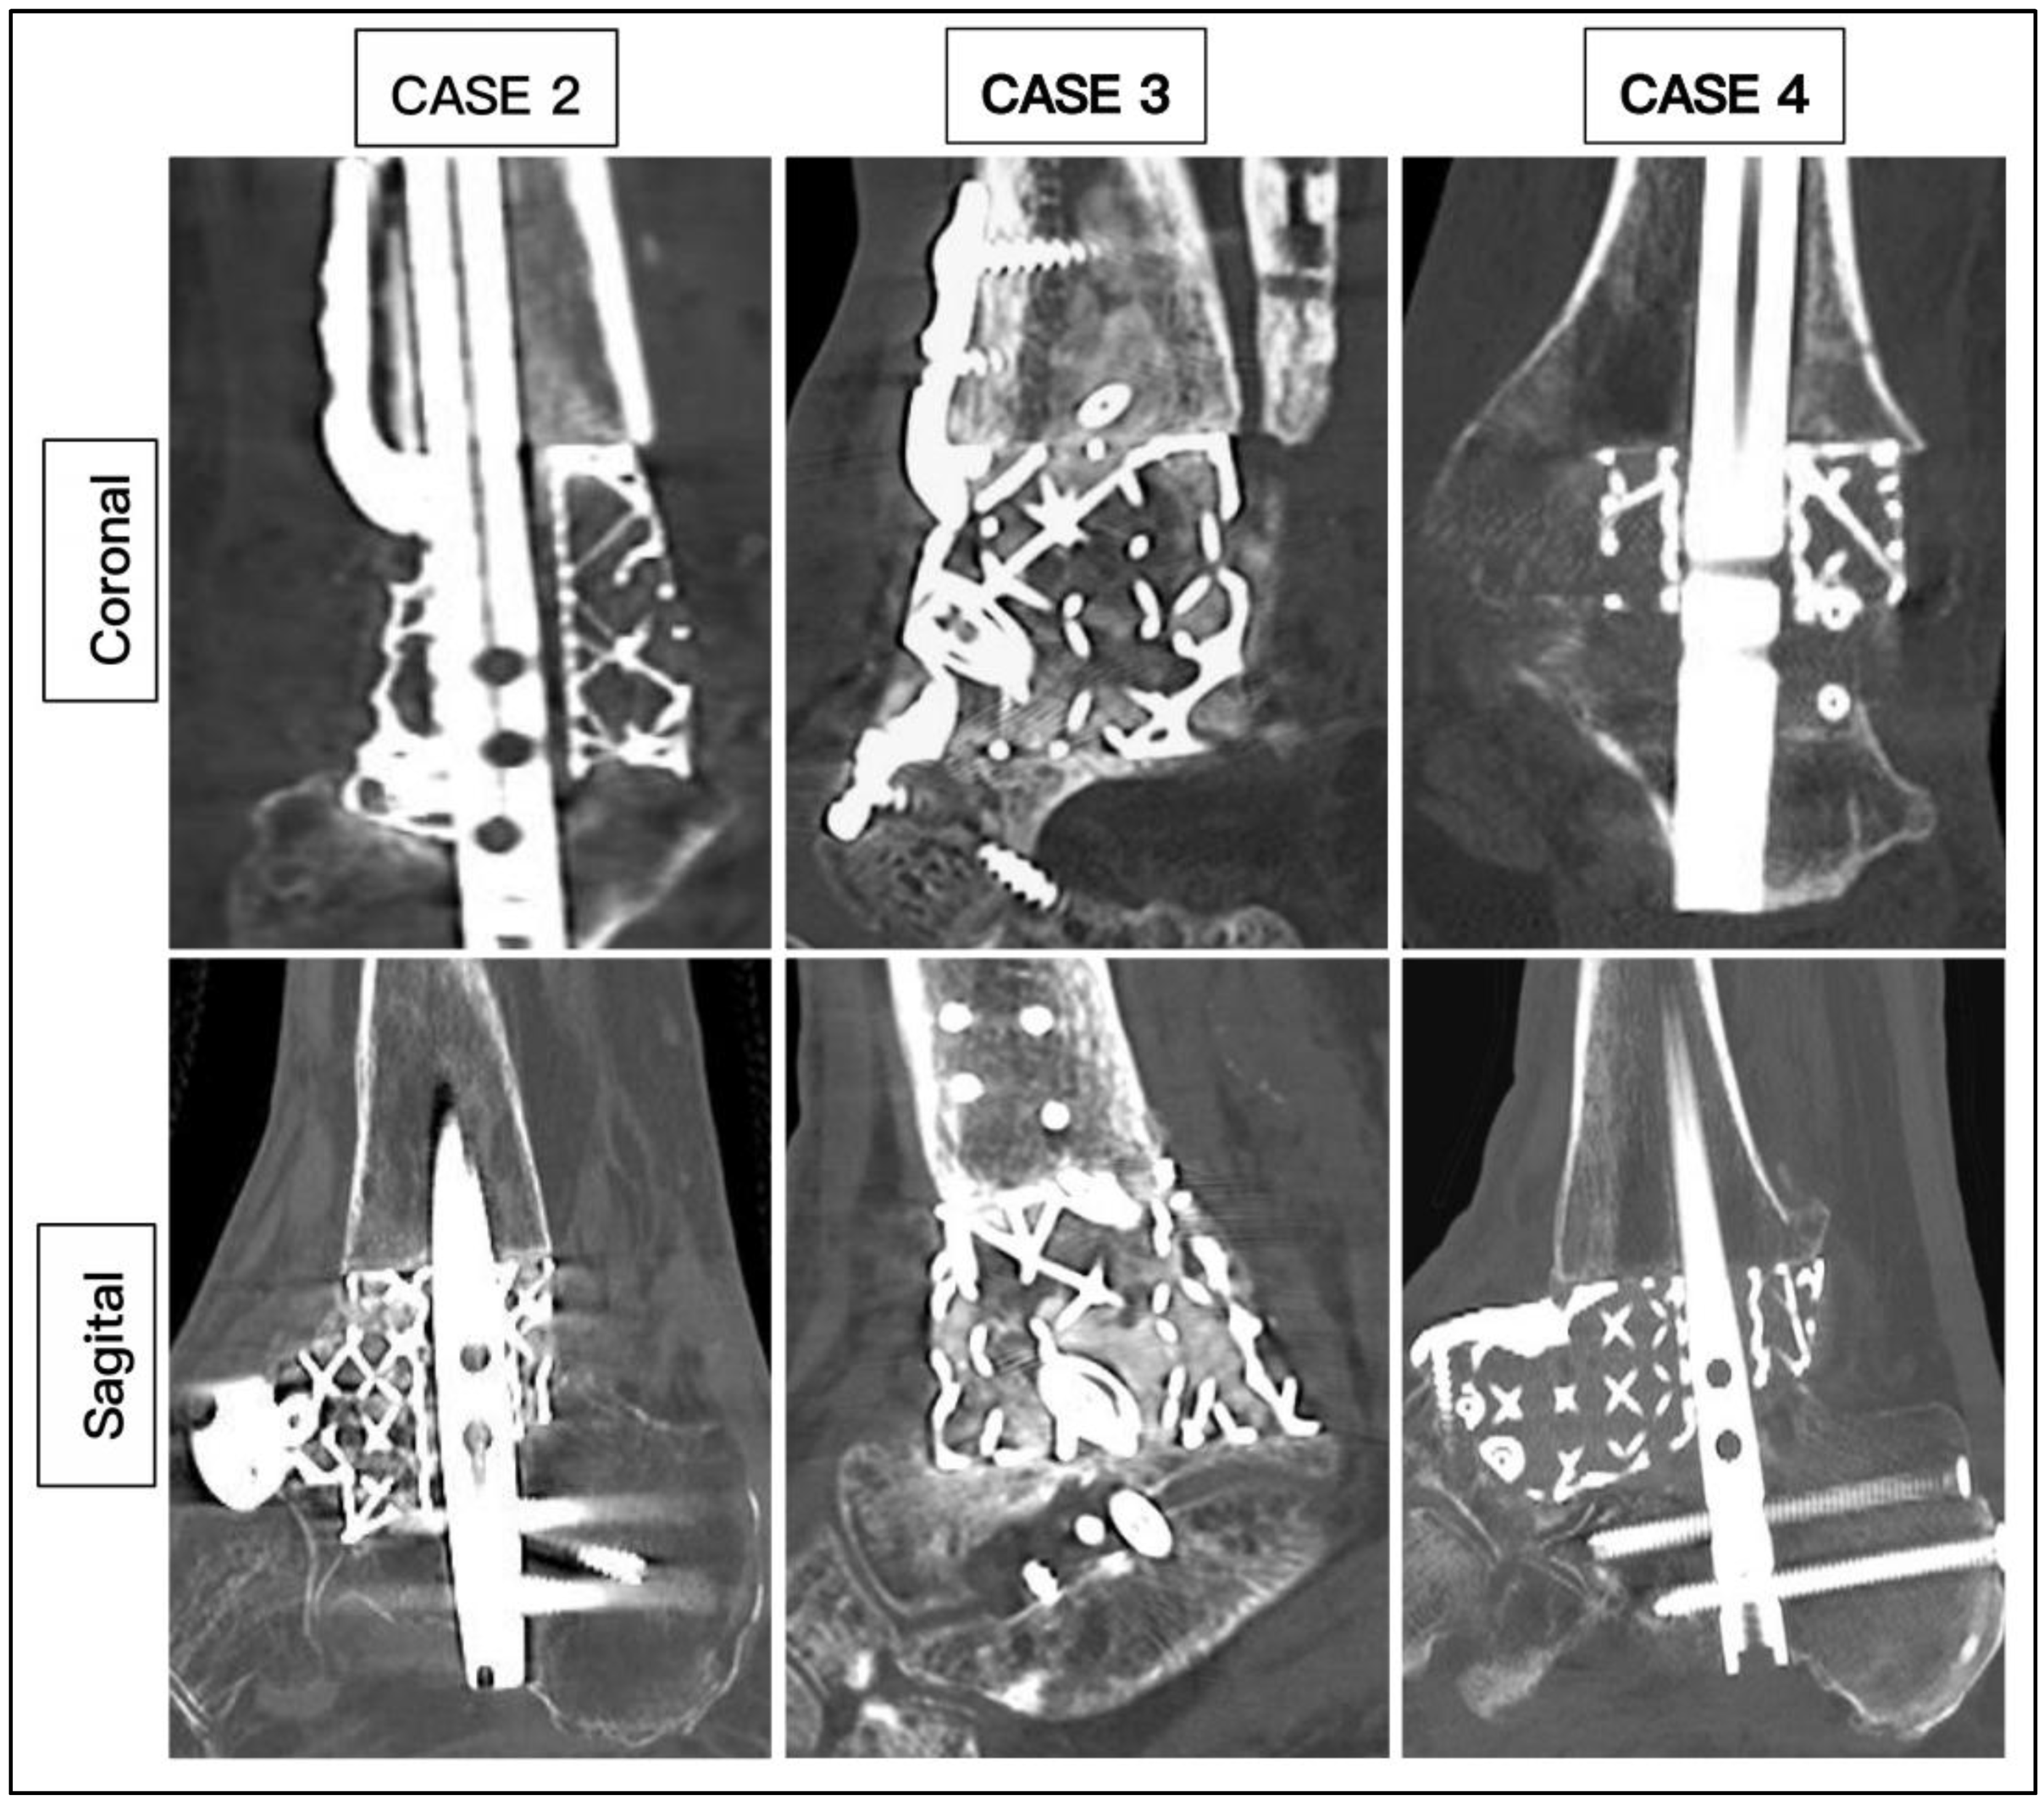

| CASE | 1 | 2 | 3 | 4 | 5 | 6 |

|---|---|---|---|---|---|---|

| Age | 62 | 59 | 60 | 60 | 78 | 67 |

| Diagnosis | OM | OM | OM | AVN | AVN | AVN |

| Smoking | No | Yes | Yes | No | Yes | No |

| BMI | 26.5 | 27.4 | 27.4 | 28.2 | 32.1 | 35.4 |

| Medical | Nil | IHD, CKD, PAD | CKD | CKD, PAD | DM | IHD, DM, CKD, CN |

| HbA1c | 36 | 39 | 39 | 41 | 49 | 70 |

| CRP | 8 | 7 | 16 | 9 | 10 | 6 |

| Hb (g/L) | 113 | 105 | 132 | 146 | 113 | 114 |

| Past surgery | 5 | 3 | 3 | 0 | 1 | 0 |

| Modification | Tibial & Navicular flange, Nail | Navicular flange, Nail | Tibial & Navicular flange | Navicular flange, Nail | Nail | Articulating Navicular extension, Tibial flange, Nail |

| Duration of surgery (Min) | 255 | 220 | 162 | 210 | 190 | 205 |

| Wound Healing (Days) - weeks | 42 | 40 | 20 | 29 | 32 | 45 |

| Union (Weeks) | 25 | 19 | 16 | 14 | 27 | 20 |

| Ambulation (Weeks) | 28 | 21 | 18 | 16 | 29 | 22 |